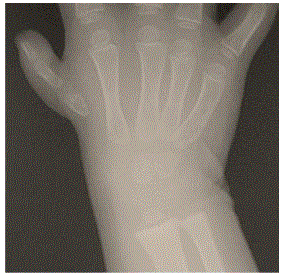

A deformidade congênita acima é classificada segundo Blauth/Manske como tipo: